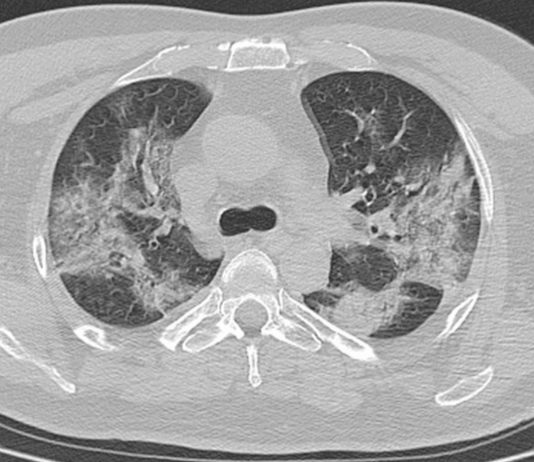

57-year-old male

patient smoker with COPD. No epidemiologic risk either exposure to Covid-19 patients.

The patient was admitted

to ED for...